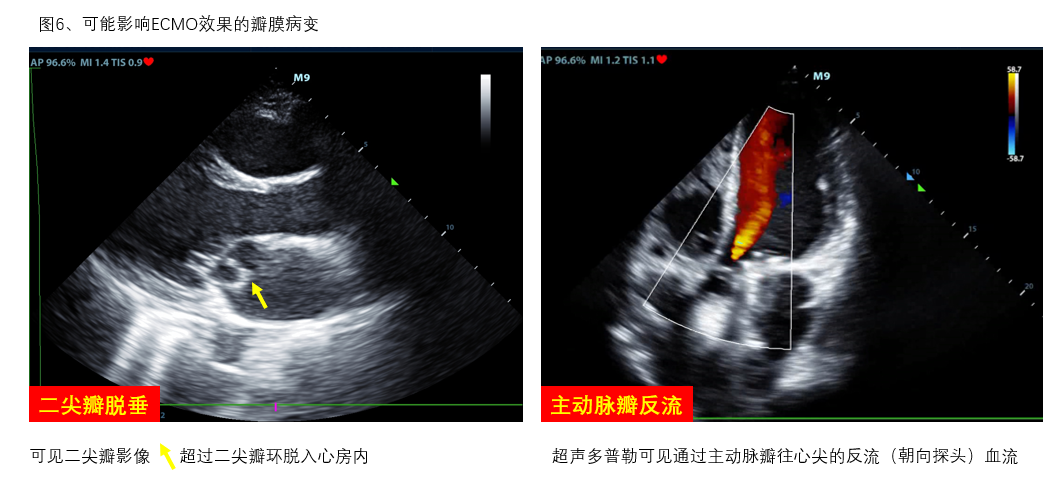

D、瓣膜 通过观察瓣膜开合节律和频率评估瓣膜功能及心律失常,二尖瓣开放程度(EPSS)协助评估左心室收缩功能。瓣膜区彩色多普勒超声可评估瓣膜反流、狭窄情况。重度主动脉瓣反流如不能短期内进行外科干预者影响VA-ECMO实施效果(图6右)。室壁无增厚的右室扩张合并急性三尖瓣、肺动脉瓣反流提示可能存在肺动脉栓塞。呼吸衰竭肺水肿者检查有无二尖瓣脱垂(图6左)、重度二尖瓣反流。不管是原发还是继发严重瓣膜问题,均可能会在ECMO实施时影响支持效率,因此,建议在ECMO准备阶段筛查瓣膜功能。

图6